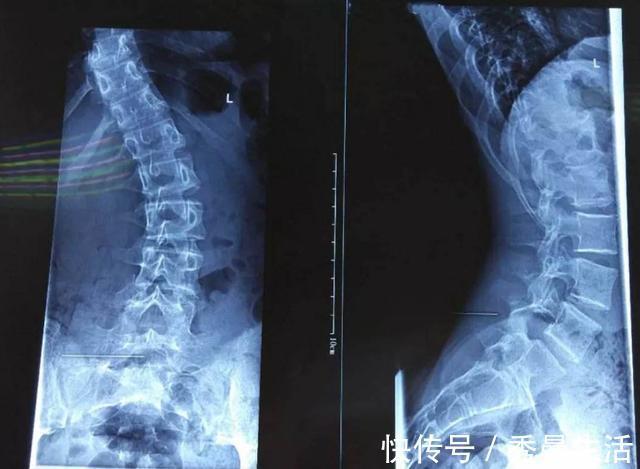

小杨本以为这是自己没有给老师送礼的原因,但在和老师进行过谈话后她得知每次女儿落选都是因为形体上的原因。小杨带着女儿去了医院,医生告诉她小杨孩子之所以形体不好,有很大一部分原因是由于小时候睡觉没有枕枕头使颈椎产生变形而造成的。听到医生这样说,小杨对自己不给孩子睡枕头的行为感到十分的后悔。

2、对颈椎造成伤害人的颈椎是具有一定的弧度的,所以当我们平躺在床上时颈椎就会呈现出一种悬空的状态,长时间这种状态会使颈椎十分的疲惫甚至产生形变,所以睡觉的时候枕枕头是对颈椎的一种保护。对于尚处于发育的孩子来说,由于头骨是非常柔软,颈椎变形也会影响到脑袋的形状。